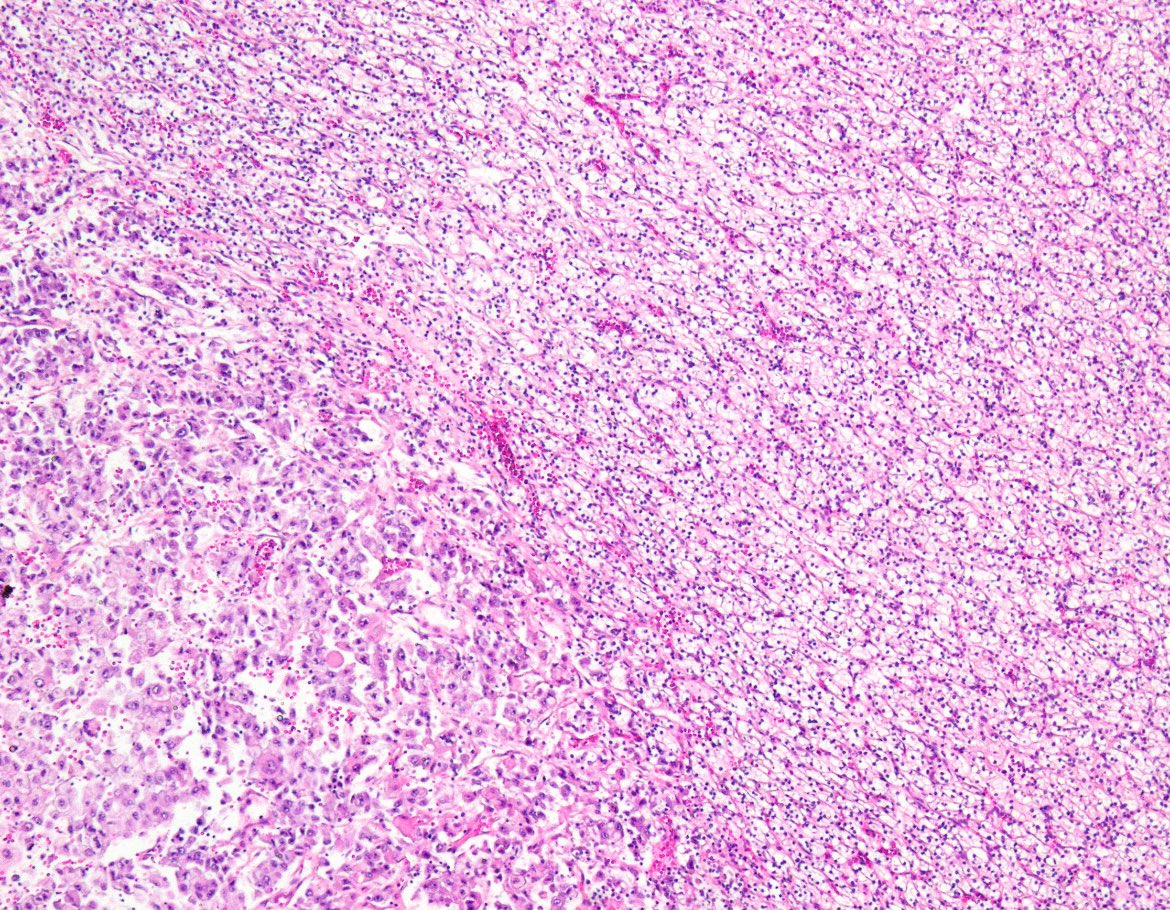

Abrupt transition from low to high nuclear grade in this Clear Cell Renal Cell Carcinoma #gupath #kidneycancer - highlighting the importance of sampling

In some Clear Cell RCC, when tumor becomes higher grade, cells become discohesive➡️'pseudo-papillary' appearance #kidneycancer #gupath In biopsies, this feature and variable clear to eosinophilic cytoplasm may raise a differential diagnosis which includes MiTF -family RCC